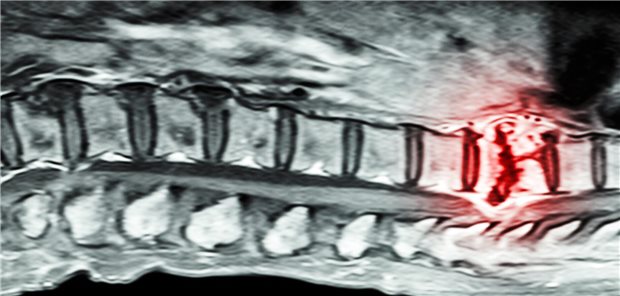

Größere Schmerzen in der frühen Kindheit scheinen mit einer Hypokonnektivität im neonatalen Gehirn verbunden zu sein, wobei die stärksten Assoziationen in den Basalganglien und den limbischen Strukturen beobachtet wurden. Eine verringerte strukturelle Konnektivität des Gehirns wurde mit schlechteren neurologischen Entwicklungsergebnissen nach 18 Monaten in Verbindung gebracht.

Sehr kleine Frühgeborene

Schmerzen beeinträchtigen die Hirnreifung – besonders bei Mädchen